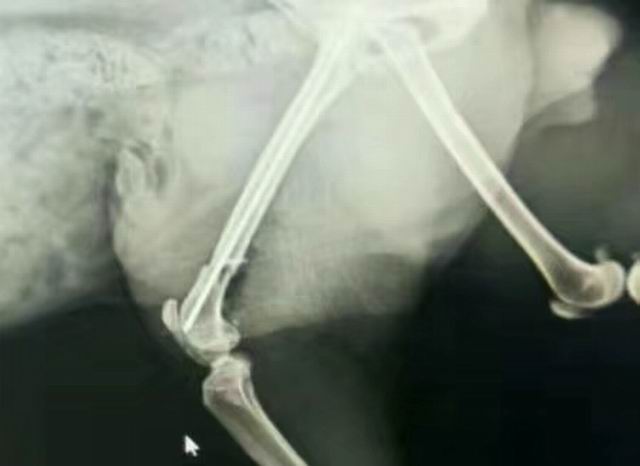

一例貓咪骨折/內(nèi)固定術(shù)

藍(lán)白,2歲,外固定失敗轉(zhuǎn)于我院,實(shí)施骨折內(nèi)固定,術(shù)前體檢+進(jìn)口麻藥+手術(shù)順利(ok),住院護(hù)理中……急主人所急,想主人所想,致力于寵物健康,洛陽狗博仕寵物醫(yī)院